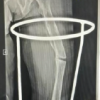

In our study, the mean age of the patients with IT fracture is 71.29 years with majority being in 71–80 years of age group (38.67%), followed by 32% in 61–70 years of age group. Among the 75 patients with IT fracture, 41 patients are males and 34 are females, amounting to 54.67% of males and 45.33% of females. In our study among 75 patients of IT fractures, 38 patients had right-side injury and 37 patients had left-side injury. Right side is common side in our study. In our study, we classified IT fractures according to Evan’s classification. Among 75 patients, 17 patients had Evan’s Type 1, Group 1 IT fracture; 21 patients had Evan’s Type 1, Group 2 IT fracture; 12 patients had Evan’s Type 1, Group 3 IT fracture; 18 patients had Evan’s Type 1, and Group 4 IT fracture and 7 patients had Evan’s type 2 IT fracture. In our study, mean operating time of PFN group is 92.80 min, MS-PFN group is 78 min and A2-PFN group is 66.8 min. Significant difference seen in PFN versus MS-PFN and PFN versus PFN-A2. There is no significant difference between MS-PFN and PFN-A2 group. In our study, mean blood loss in PFN group is 307.2 mL; in PFN-A2 group, it is 237.2 mL and in MS-PFN group, it is 246.4 mL. Significant difference is seen in PFN versus MS-PFN and PFN versus PFN-A2. There is no significant difference between MS-PFN and PFN-A2 group. In our study, mean radiological union in PFN group is 15.89 weeks; in MS-PFN group, it is 14.92 weeks; and in PFN-A2 group, it is 13.14 weeks. There is significant difference between PFN and PFN-A2 group in terms of union. In our study, we compared Harris hip score among three groups at post-operative 6 weeks, 12 weeks, 6 months, and 1 year. The results are tabulated in Tables 2 and 3, Graph 1. There is significant difference between PFN and PFN-A2 group in terms of functional outcome. In our study, we compared anterior thigh pain among three groups. Anterior thigh pain is more in PFN with 52%, followed by PFN-A2 with 40% and less in MS-PFN group with 27% (Table 4). PFN group had 12% shortening, 8% of screw cut out, 8% of SSI, 4% of varus collapse, and 4% of Z effect/reverse Z effect. PFN-A2 group had 4% shortening, no screw cut out, 8% of SSI, and 4% of varus collapse. MS-PFN group had 8% shortening, 4% of screw cut out, no SSI, no varus collapse, and 4% of Z effect/reverse Z effect (Table 5).

The average intraoperative blood loss in PFN group was 307.20 mL. PFN-A2 group had an average blood loss of 237.20 mL and MS-PFN had an average blood loss of 246.40 mL. Average blood loss was least in PFN-A2. In a study on PFN by Chopra et al. [10], average blood loss during surgery is 126 mL. In a study on MS-PFN by Jha and Ahmed [6], average blood loss is 130 mL and in a study on PFN-A2 by Rai et al. [11], average blood loss is 200 mL. In our study average radiological union in PFN group is 15.89 weeks; in MS-PFN group, it is 14.92 weeks and in PFN-A2 group, it is 13.14 weeks. Union in PFN-A2 is earlier compared to PFN and MS-PFN. In a study on PFN by Gadegone and Salphale [12], average time for fracture consolidation is 18 weeks. In a study on MS-PFN by Jha and Ahmed [6], average time for radiological union is 17.32 weeks and in a study on PFN-A2 by Rai et al. [11], it is 13.8 weeks. In our study, average mean Harris hip score for PFN-A2 is higher compared to PFN and MS-PFN at post-operative 6 weeks, 12 weeks, 6 months, and at 1 year. Harris hip score for PFN at 1 year is 82.26, for MS-PFN, it is 86.18, and for PFN-A2, it is 88.81. At post-operative 1 year, Harris hip score is higher in PFN-A2 group, followed by MS-PFN group compared to PFN group. All three implants have given good functional outcome according to Harris hip score. In a study on PFN by Mandice et al. [13], Harris hip score at 6-month post- operative is 88.75 and in a study on PFN-A2 by Rai et al. [11], it is 85.08 at 6-month post-operative. In our study, among 25 patients of PFN, 13 patients had persistent anterior thigh pain, among 25 patients of PFN-A2 of 240 mm, 15 patients had anterior thigh pain. However, in our MS-PFN group, it was significantly low, only 4 patients complained of anterior thigh pain out of 25 patients. In a study on PFN by Mukherjee et al. [14], 16 out of 53 patients had anterior thigh pain. In a study on PFN-A2 by Kumar et al. [15], 3 among 25 patients experienced anterior thigh pain. In our study, among 75 patients, 3 in PFN group, 2 in MS-PFN group, and 1 in PFN-A2 group had >1 cm of shortening. In a study on PFN by Chopra et al. [10], out of 125 patients, 3 had shortening. In a study on MS-PFN by Jha and Ahmed [6] out of 120 patients, 9 patients had shortening. Moreover, in a study on PFN-A2 by Rai et al. [11], among 25 patients, 2 patients had shortening. 2 patients in PFN group and 1 in MS-PFN group had complication of screw cutout; 2 in PFN group and 2 in PFN-A2 group had surgical site infection; 1 in PFN group and 1 in PFN-A2 group had varus collapse; and 1 in PFN group and 2 in MS-PFN group has Z effect/reverse Z effect. In a study on PFN by Chopra et al. [10], out of 125 patients, 5 had Z effect/reverse Z effect. In a study on MS-PFN by Jha and Ahmed [6] out of 120 patients, 14 patients had above-mentioned complications and in a study on PFN-A2 by Rai et al. [11], among 25 patients, 2 patients had varus collapse and 1 patient had surgical site infection.